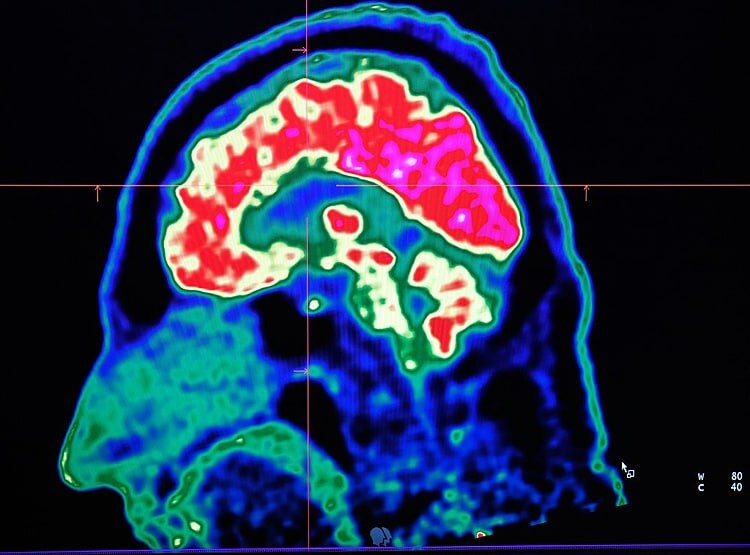

एड्रियन ओवेन ने कहा कि अगर कोई ये सोचता है कि दिमाग पर असर कुछ ही दिन रहेगा तो वो गलत होगा. हमें नहीं पता कि कोरोना वायरस की वजह से दिमाग पर होने वाले दुष्प्रभाव कितने सालों तक रहेंगे. (फोटोः गेटी)

इस स्टडी को करने वाले वैज्ञानिकों का कहना है कि दुनियाभर के डॉक्टरों को कोरोना वायरस से जूझ रहे और रिकवर हो चुके मरीजों के दिमाग की जांच भी करनी चाहिए. ताकि पता चल सके कि यह खतरनाक वायरस मरीजों के दिमाग पर किस तरह का असर डाल रहा है. (फोटोः गेटी)